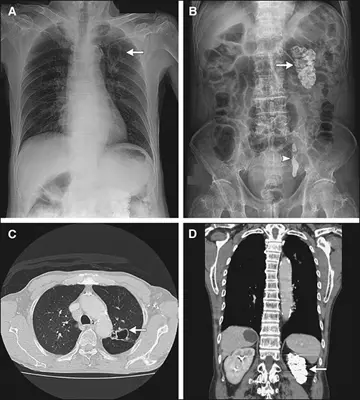

سل کلیه